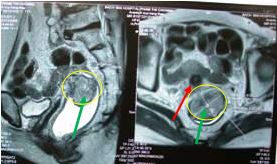

Khối u trực tràng trước điều trị chiếm toàn bộ chu vi (mũi tên màu xanh), và có hạch cạnh trực tràng

(mũi tên màu đỏ)